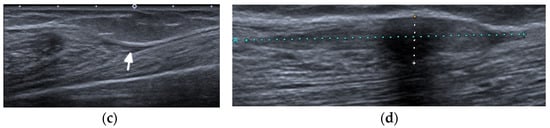

Figure 4.

A 64-year-old female with SLE diagnosed in 1980 with Jaccoud’s arthropathy for hands and feet. (a) Posterior–anterior and (b) oblique radiographs of the hands show bone demineralization; soft tissue swelling at the wrists; periarticular calcifications; malalignment at the distal radioulnar, radiocarpal, and midcarpal joints; dislocation of the 1st carpometacarpal and subluxation of the 1st metacarpophalangeal joints; and joint space narrowing with cyst-like and erosive/destructive changes consistent with rhupus syndrome. Note the reversible contractures at the proximal interphalangeal joints, apparent in (b) and resolved or less apparent in (a). (c) Anterior–posterior standing radiograph of the bilateral feet and (d) lateral standing radiograph of the left foot show bone demineralization, bilateral hallux valgus deformities, and bilateral 2nd and 3rd hammer toes, as well as a right foot with moderate lateral subluxation.